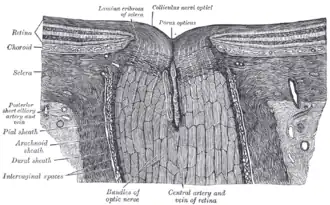

The terminal portion of the optic nerve and its entrance into the eyeball, in horizontal section. | |

The ganglion cell axons form the optic nerve after they leave the eye. The optic disc represents the beginning of the optic nerve and is the point where the axons of retinal ganglion cells come together. The optic disc in a normal human eye carries 1–1.2 million afferent nerve fibers from the eye toward the brain. The optic disc is also the entry point for the major arteries that supply the retina with blood, and the exit point for the veins from the retina.[1]

The optic disc is located 3 to 4 mm to the nasal side of the fovea. It is a vertical oval, with average dimensions of 1.76mm horizontally by 1.92mm vertically.[2] There is a central depression, of variable size, called the optic cup. This depression can be a variety of shapes from a shallow indentation to a bean pot—this shape can be significant for diagnosis of some retinal diseases.